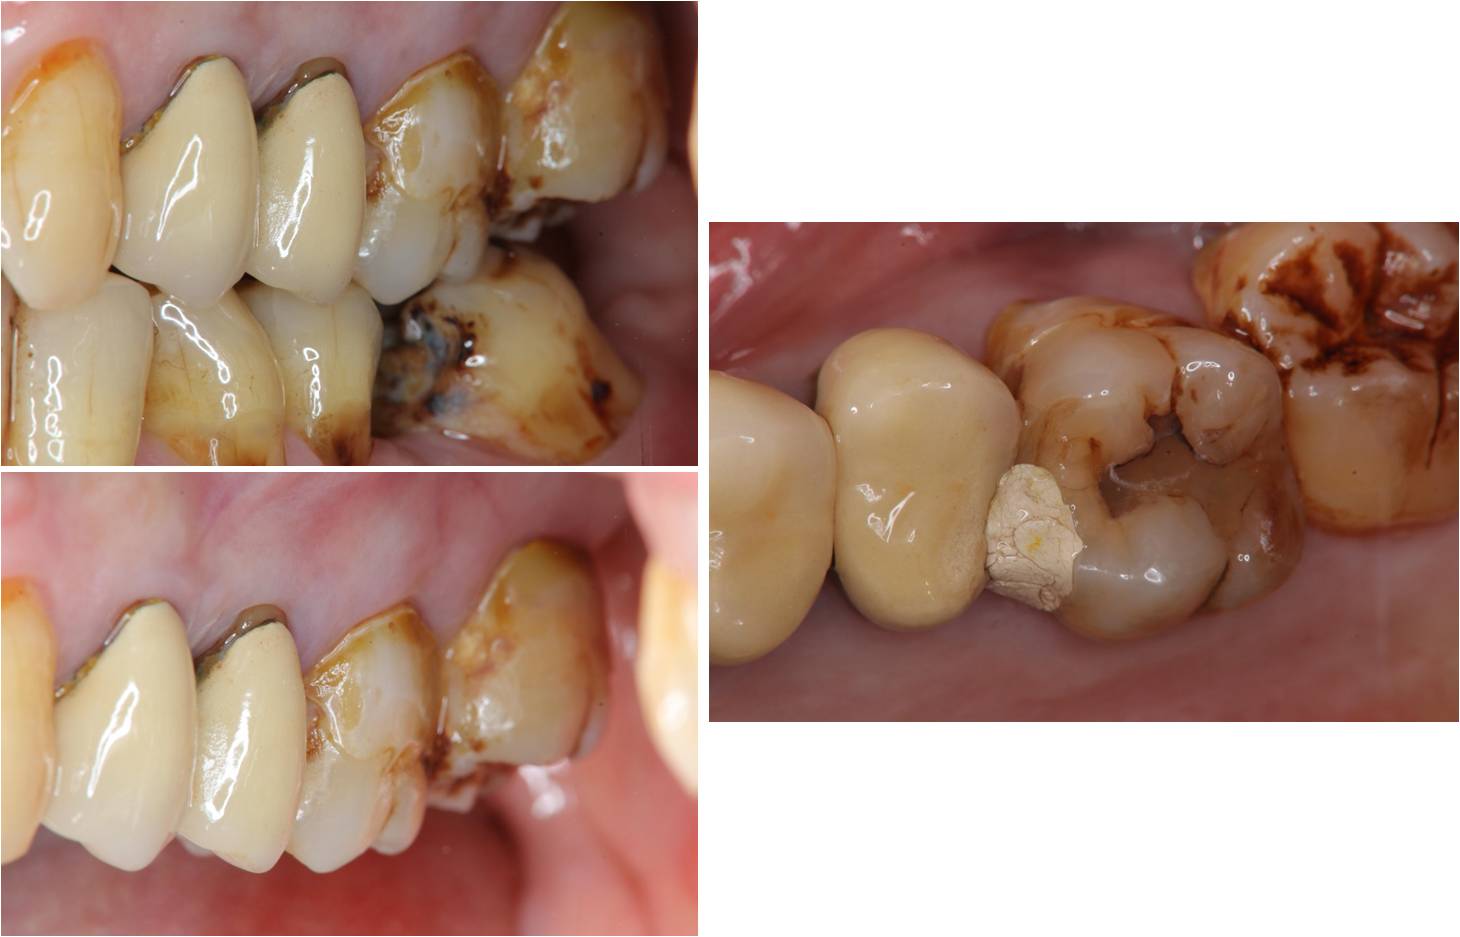

治療前,牙齦下蛀牙

蛀牙至牙髓